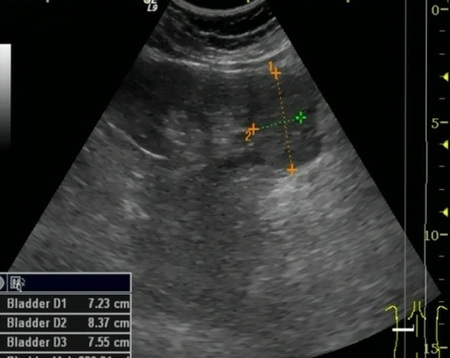

Рис. №1. УЗИ левой почки. Опухоль нижнего сегмента левой почки до 5 см.

Из анамнеза: по месту жительства при УЗИ органов мочеполовой системы заподозрено образование левой почки. Консультирована в клинике урологии Первого МГМУ им. И.М. Сеченова, при УЗИ и МСКТ органов брюшной полости наличие образования в нижнем сегменте левой почки подтверждено. Госпитализирована в онко-урологическое отделение в плановом порядке для выполнения оперативного пособия.